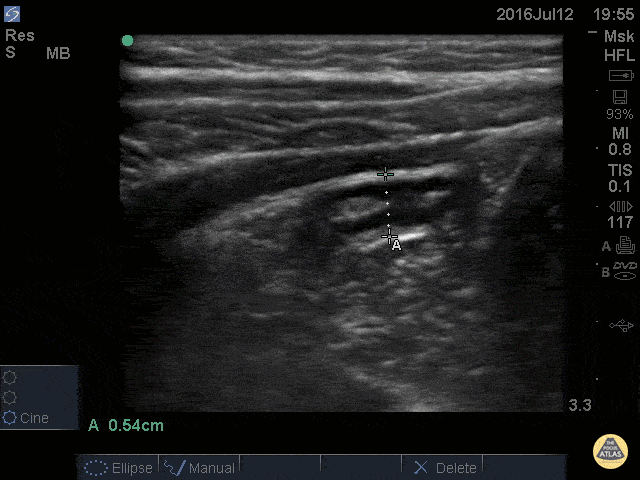

Peds-Gastrointestinal - Normal Appendix - Cross Section Measured

14 y/o M with nausea vomiting and and RLQ pain. POCUS visualized a normal appendix is seen. A normal appendix is identified by a blind-ending tubular structure that is <6mm diameter measured from outer wall to outer wall (although 6mm-7mm has also been described). This patient’s appendix was measure to be 5.4mm. Dr. Sathya Subramaniam - Children’s Hospital of Philadelphia